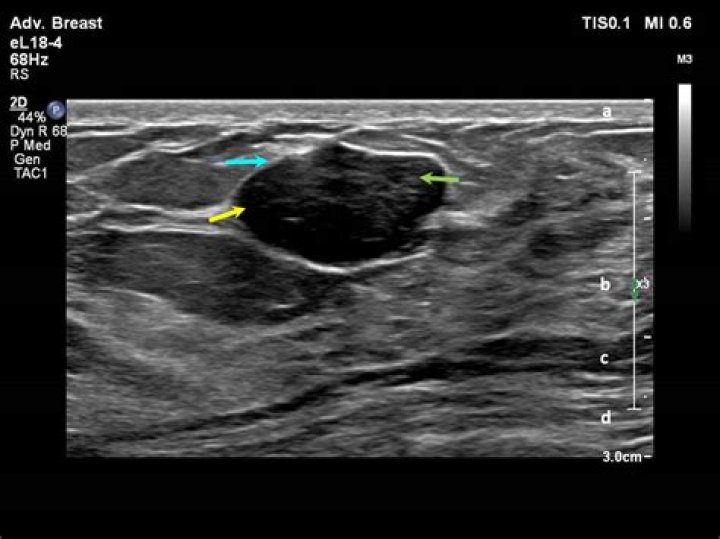

What is a circumscribed hypoechoic mass

A hypoechoic mass is tissue in the body that’s more dense or solid than usual. This term is used to describe what is seen on an ultrasound scan. Ultrasound uses sound waves that are absorbed by or bounce off of tissues, organs, and muscles.

Solid masses are hypoechoic and can be cancerous. Cysts filled with air or fluid are usually hyperechoic and are rarely cancerous. Abnormal tissue also looks different from healthy tissue on a sonogram. Your doctor will usually do further testing if an ultrasound shows a solid mass or what looks like abnormal tissue.

As defined in the US lexicon (1), circumscribed margins are well defined or sharp, with an abrupt transition between the lesion and the surrounding tissue. Noncircumscribed margins encompass the remaining margin descriptors, including microlobulated, indistinct, angular, and spiculated.

On ultrasound, a breast cancer tumor is often seen as hypoechoic. It has irregular borders, and may appear spiculated. Other ultrasound findings that suggest breast cancer include: Nonparallel orientation (not parallel to the skin)